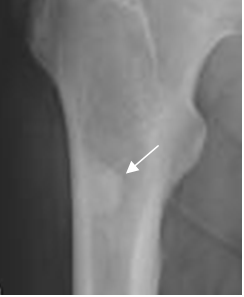

Fig 57. Osteoma.

Rx AP. Lesión densa y homogénea, en la diafisis femoral, de localización excéntrica, por osteoma.